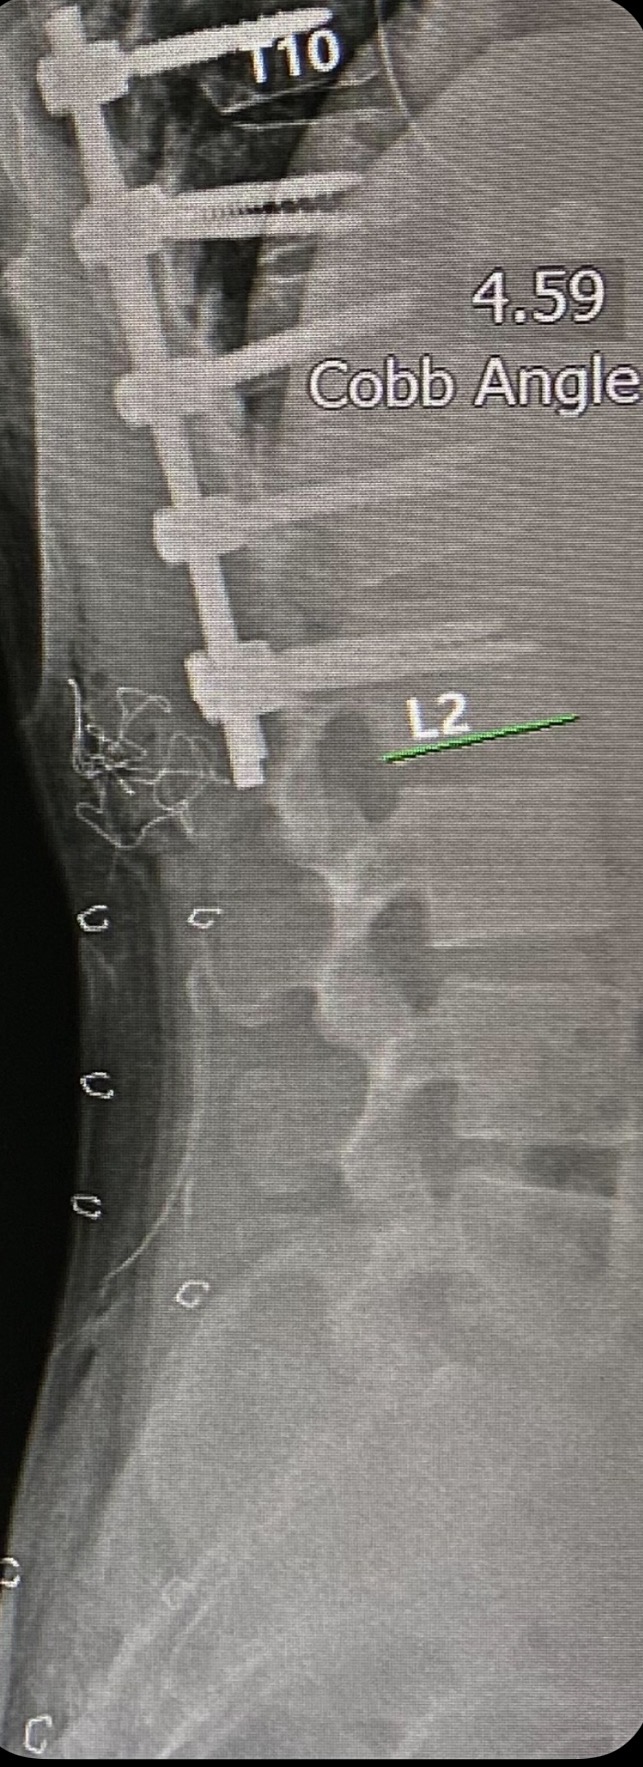

측만증이랑 다른건가... 받는 수술은 비슷하네. 저거 별거 아닌 것 같아도 저승문 터치하고 오는거 맞지..